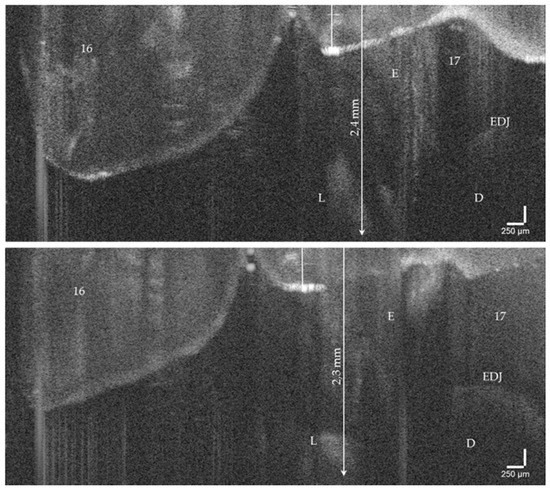

Figure 6.

OCT cross-sectional image of an early approximal enamel carious lesion (L; ICDAS, Code 2) on tooth 17 in vivo. The lesion can be localized to a depth of 2.4 mm below the enamel surface. As a result of focusing on deeper structures, the tooth surface is flipped over again. Enamel (E), dentin (D), enamel-dentin junction (EDJ). The vertical scales are related to refractive index n = 1.0 (see the remark in Figure 4).

On hard tooth tissues, the imaging depth was up to 2.5 mm (Figure 6). The spatial resolution of the probe also partially allowed the visualization of superficial tissue structures of the gingiva (Figure 4e,f). The 90°-optics and the ergonometric design of the probe allowed the dentist to manually image all occlusal, vestibular, oral, and proximal tooth surfaces including those of the second molars and the occlusal, oral and proximal surfaces of the third molars. The vestibular surfaces of third molars and proximal surface areas of the molars within a “blind spot” at a distance greater than 2.5 mm from the tooth surfaces could not be imaged. While a B-scan is recorded in real time, the scan time for a C-scan is approximately 28 seconds.